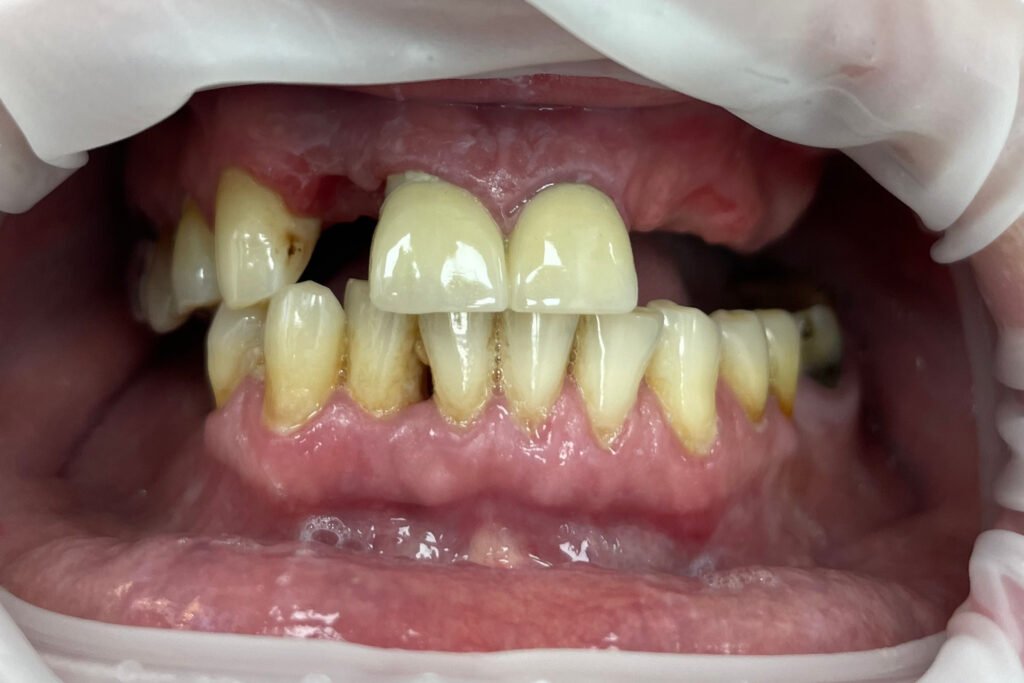

Ситуация до лечения

Жалобы: Пациент обратился к нам с целью проведения комплексной имплантации верхней челюсти.

Диагноз: Частичная вторичная адентия верхней челюсти.

пациент до протезирования